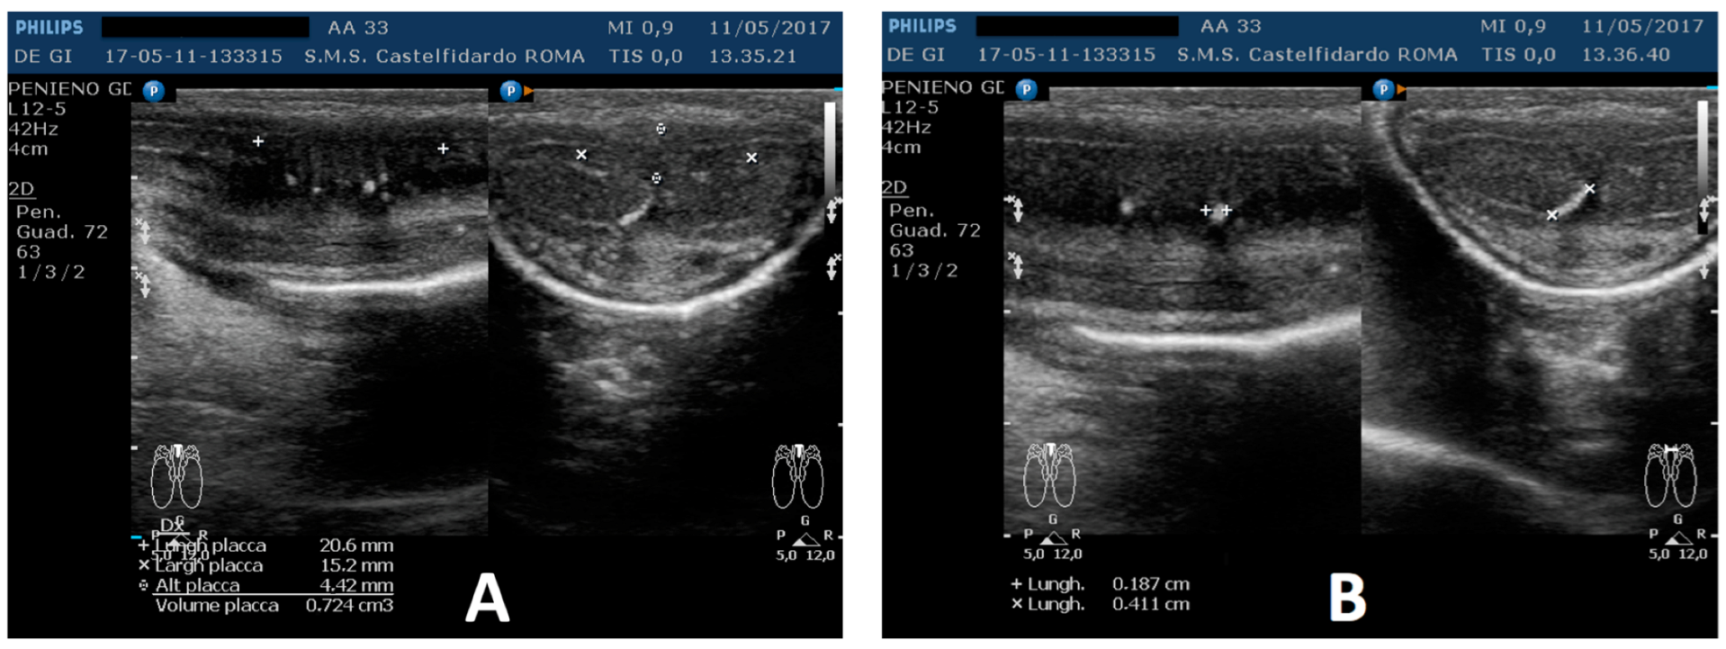

| 3 | 33 years | None | Middle third | (A) 20.6 × 15.2 × 4.42 mm volume = 724 mm3 + some small calcifications, the largest of which measured 1.9 × 4.1 mm | (A) 30-degree dorsal penile curvature | (A) score 2 | (A) score 26 | 3 years and 5 months | orally: Silymarin 400 mg + Ginkgo biloba 250 mg + Propolis 600 mg + Bilberry 160 mg + Vitamin E 800 IU/once a day, for 41 months. + topically: Propolis creme/twice a day/for 41 months. + peri-plaque penile injections: Pentoxifylline 100 mg (30 G needle) every 15 days for 6 months, and then monthly for 12 months, and then 1 injection every other month. for 12 months (total = 30 injections) |